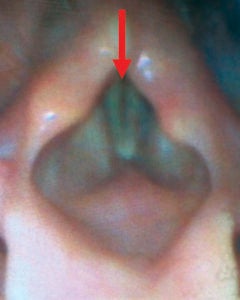

HIDI Study 1 Fig 1